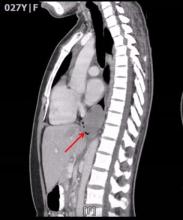

A 27-year-old woman underwent a video-assisted thoracoscopic enucleation of a giant horseshoe esophageal leiomyoma. The patient was asymptomatic and the lesion was discovered incidentally on a routine chest radiograph. Computed tomography (CT) of the thorax showed a 5.5 cm polypoid soft tissue mass in the distal third of the esophagus, causing narrowing and deviation of the lumen anteriorly. Esophagogastroduodenoscopy revealed a large submucosal mass at the distal third of the esophagus. The lesion was imaged as a 45 mm x 25 mm hypoechoic, inhomogeneous mass arising from the muscularis propria on endoscopic ultrasound. Fine needle aspiration (FNA) of the tumor showed a spindle cell tumor consistent with a leiomyoma.